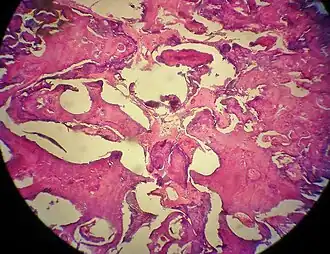

Description de l'image Odontoma.jpg.

Une odontomie, généralement appelé odontome est une tumeur bénigne[1] liée au développement des dents[2]. Plus précisément, il s'agit d'un hamartome dentaire, ce qui signifie qu'il est composé de tissu dentaire normal qui s'est développé de manière irrégulière. Il comprend à la fois les tissus odontogènes durs et mous. Comme pour le développement normal des dents, les odontomes cessent de croître une fois matures, ce qui les rend bénins[3].

L'âge moyen des personnes trouvées avec un odontome est de 14 ans[4]. La condition est fréquemment associée à une ou plusieurs dents qui n'ont pas fait rompre et est souvent détectée par l'incapacité des dents à faire éruption au moment prévu. Bien que la plupart des cas soient touchés dans la mâchoire, il existe des cas où des odontomes ont éclaté dans la cavité buccale[5].